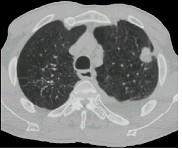

问题 女,64岁,胸背疼痛1周,CT检查如图,最可能的诊断为 ( )

选项 A.左上肺结核球 B.左上肺周围型肺癌 C.左上肺炎性假瘤 D.左上肺单发性转移癌 E.左上肺错构瘤

答案 B